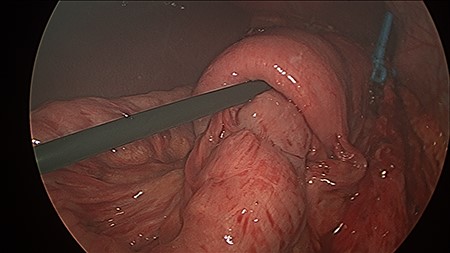

The patient was positioned supine, and cut down entry periumbilically was performed with a 10-mm camera port and two 5-mm working ports inserted. On laparoscopy, a retrograde intussusception with the intussuscipien constituted the gastric pouch and the intussusceptum constituting the alimentary limb of the jejunum was identified. Just distal to the intussusceptum, there was a jejunal mesenteric defect, with demonstrable thinning of mesenteric fat and various tears. Through this defect, the remnant stomach, normally situated on the left side of the gastric pouch, was found to have herniated from the left to right through this jejunal mesenteric defect, posterior to the alimentary limb in the supracolic compartment. This internal hernia was reversed and the defect closed with non-dissolvable V-Loc™ barbed sutures. A slipped MiniMizer gastric ring was then identified 3 cm distal to the gastrojejunal anastomosis (Fig. 2). No fixation sutures were identified. On release of the ring, 25 cm of alimentary limb jejunum was, with gentle traction, pulled from its invagination into the gastric pouch through where the ring was originally placed (Fig. 3). Surprisingly, all bowel was viable and no resection was required.

This figure demonstrates operative findings prior to surgical manipulation. The MiniMizer band is present at forefront, 3 cm distal to gastrojejunal anastomosis. The intussusception and internal herniation may be difficult to appreciate from this image.